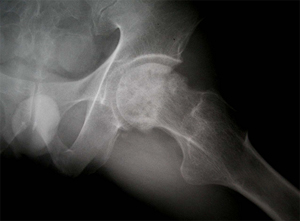

상기 환자는 46년 전부터 고관절 통증이 있었으며, 12년전 Lt. total hip replacement(THR)을 받은 분으로 2년 전부터 통증으로 인해 물리치료를 받았지만 통증이 지속되었고, 본원 OS 외래에서 방사선 촬영하여 Lt. THR loosening 소견으로 revision O.P. 위해 입원하여 O.P.이후 재활위해 물리치료실로 의뢰됨

• 수술 전 고관절 X-선 수술 전 고관절 X-선 사진